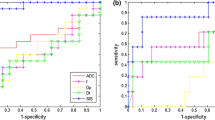

The best results to predict pathological complete response were obtained by CBFM Dp mean value pre-treatment, VARPRO Fp mean value pre-treatment and for VARPRO Dp mean value pre-treatment (Fig. 2a–c) with area under ROC of 0.71, 0.68 and 0.84 (Table 3), respectively.

The best results to predict responders were obtained by CBFM Fp mean value pre-treatment, CBM Dp standard deviation value pre-treatment and for VARPRO Dp mean value pre-treatment (Fig. 2d–f) with area under ROC of 0.63, 0.63 and 0.65 (Table 3), respectively.

The best results to detect after treatment complete pathological response were obtained by SIS, the percentage change in MK standard deviation and by percentage change in VARPRO Dp mean value (Fig. 3a–c) with area under ROC of 0.89, 0.70 and 0.72 (Table 4), respectively.

The best results to differentiate responders vs. non-responders after treatment were obtained by SIS, the percentage change in MK standard deviation and percentage change in VARPRO Dp mean value (Fig. 3d–f) with area under ROC of 0.94, 0.60 and 0.65 (Table 4), respectively.